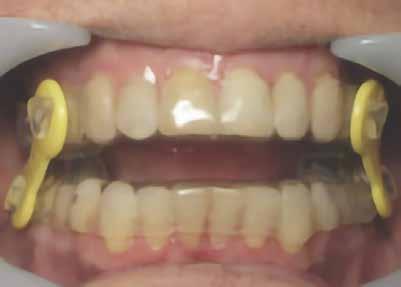

tegek orális készülékterápiával (OAT) történő sikeres kezelésében [17]. Az orrlégúti elzáródás közvetlenül öszszefügg a nappali fáradtsággal [18]. Az i-CAT képalkotó szoftver lehetővé teszi az oropharyngeális légutak volumetrikus értékelését. Ennek a betegnek a kapott adatok alapján súlyosan veszélyeztetett légútja volt, minimum 61,3 mm-rel. A színskála azt mutatja, hogy az értékelés alsó határa 100 mm (9–11. ábra). Kezelési tervünkben OAT (EMA II), fül-orr-gégészeti konzultáció és egy nyomon követő alvásvizsgálat szerepelt. Az FDA által jóváhagyott alvásfogászati készülék 2012. szeptember 5-én került szállításra (12. ábra). A Sibilant Phoneme (Sziszegő fonéma) harapásregisztrációs technikát használtuk a készülék elkészítésének a kiinduló helyzeteként, mivel ez fiziológiai, nem pedig konstrukciós technika. Ez az egyetlen olyan harapásregisztrációs technika, amely bizonyítottan és szakmailag lektorált folyóiratban publikálva jelent meg. Ennek a harapásregisztrációs technikának lényege, hogy megnyitja a légutakat, de amely a legfontosabb, csökkenti azok összeesését [19]. Az OSA-ban szenvedő betegeknél a légzés kizárólag csak alvás közben áll le, ezzel szemben ébrenlét közben soha nem áll le. Így az oropharyngealis légutak térfogata kevésbé fontos, mint azok összeesése. Ez azt jelenti, hogy ritkán van szükség titrálásra, ha a fonetikus harapásregisztrációt kiindulási pontként használjuk. Ez a páciens tökéletes példa erre, mivel az ő készülékét soha nem kellett titrálni. Az orofaringeális térfogatok (13. ábra) az ébrenléti kiindulási állapotban és a harapásregisztrációval csak kis különbséget mutatnak, azonban az

12. ábra: Páciens és az alvásfogászati készülék.

13. ábra: A légutak méretei (balra) és a harapásregisztráció (jobbra).